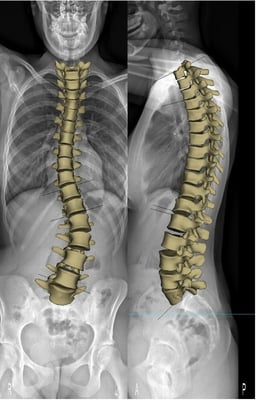

Bildlegende, von links: Röntgen mit Korsett, Röntgen von vorne/seitlich, Röntgen mit ausgeprägter Skoliose